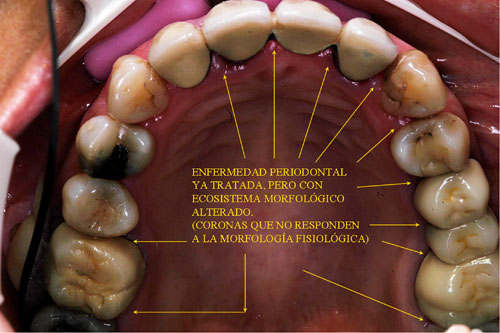

Los tejidos paradenciales muestran una recesión múltiple en todos los cuadrantes, estando tratada por el Periodoncista mediante raspajes y curetajes.

Carencia de Anatomía Coronaria

Canino que no cumple su Función Desoclusiva

Incisivo que no cumple su Función Desoclusiva